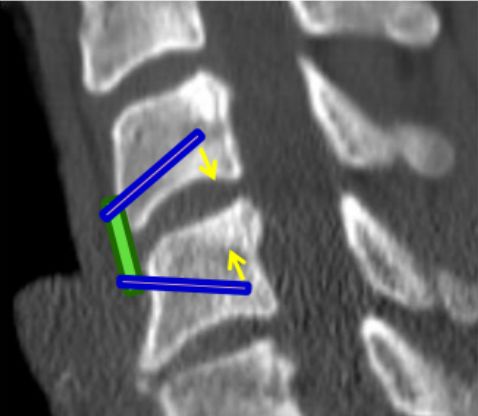

前板需选择适当的尺寸,避免过长延伸影响到相邻的椎间盘空间。

矢状面上将螺钉置于“发散”状态以使压力传递到椎间植入物上。

轴位平面上将螺钉内聚(“三角”)放置以防止拉出。